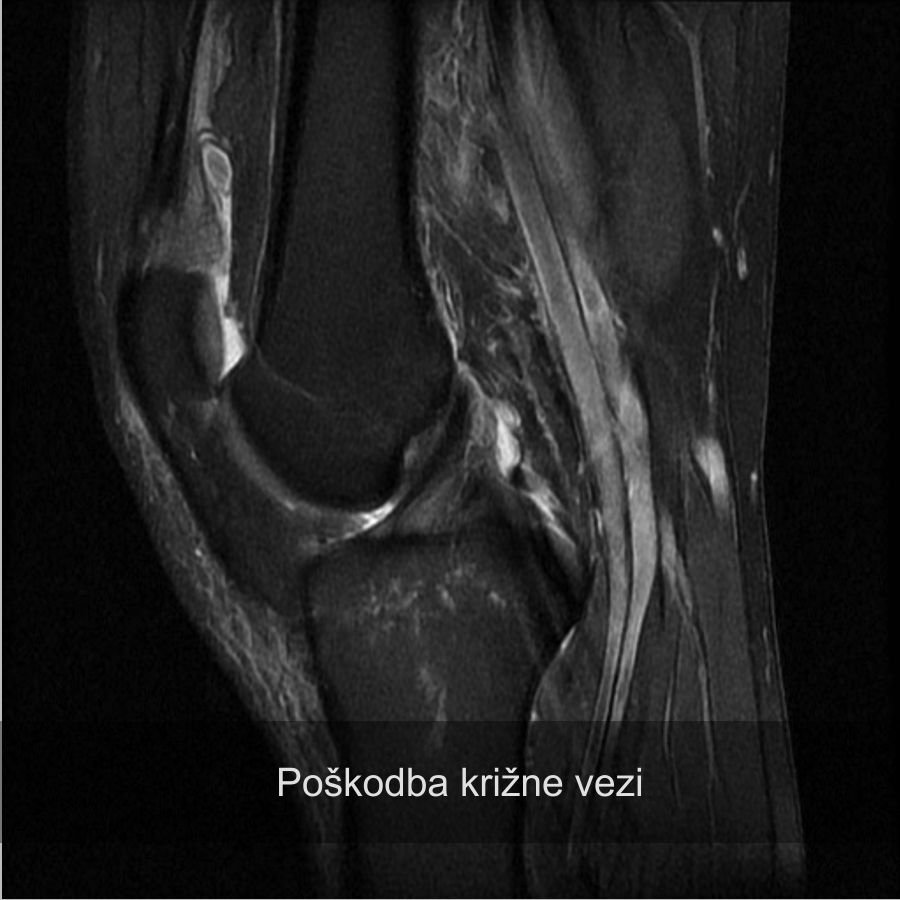

Poškodba sprednje križne vezi, operacija kolena, robi kelc

Poškodba križne vezi

Rekonstrukcija križne vezi